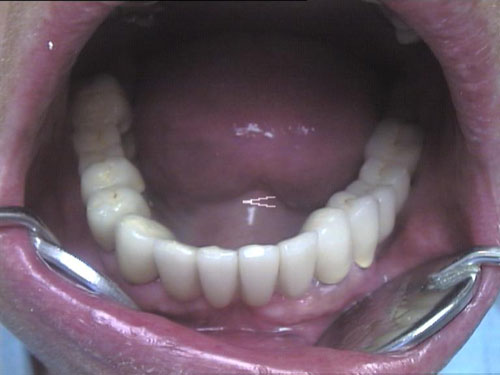

Zahn-Anomalien 1

Zahn-Anomalien 2

Zahn-Anomalien 3

Zahn-Anomalien 4

Zahn-Anomalien 5